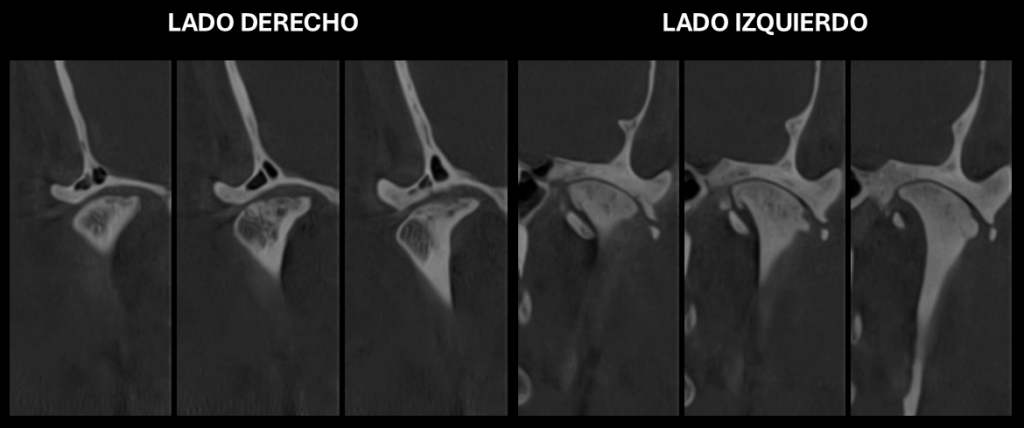

En la ampliación imagenológica con tomografía computarizada de haz cónico se identifica en el lado derecho se aprecia aplanamiento y esclerosis de la cabeza condilar, con formación de osteofito, presencia de pseudoquiste subcondral y erosión en el contorno superior, además de una disminución del espacio articular en las regiones posterior y lateral. En el lado izquierdo se observa aplanamiento y esclerosis que comprometen la cabeza y el cuello condilar, con osteofito asociado y múltiples cuerpos óseos libres alrededor del cóndilo. Asimismo, se identifica una reducción del espacio articular en las regiones posterior, superior, medial y lateral.

Cortes Sagitales Oblicuos